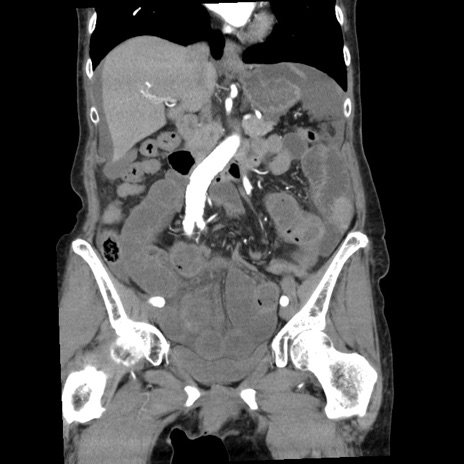

症例1(冠状断像)

【症例】80歳代女性

【主訴】腹痛

【現病歴】8時間前から腹痛あり来院。

【既往歴】糖尿病、脂質異常症、子宮体癌にて子宮全摘術

【身体所見】意識清明・会話良好だが腹痛で苦悶様、全腹部にわたって反跳痛と圧痛あり

【データ】WBC 13600、CRP 0.14、LDH 224、CK 90